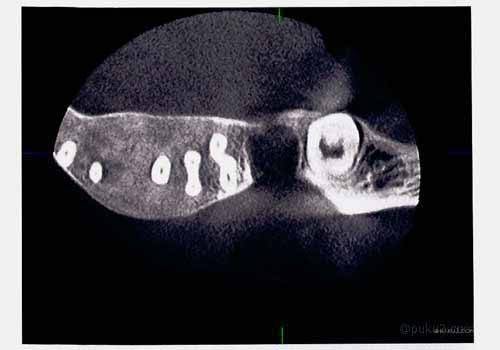

さて、こちらの画像をご覧あれ。

いきなりグロいですかね(笑

虫歯の治療だらけの汚いレントゲン画像ですみません。これが30代半ばのときのキノコ隊長の歯です。Lの字が薄いですが、左の奥歯のところがすっぽり抜けてます。まぁまぁ、虫歯を放置すると年齢関係なくこうなる可能性があるということですね。

そんな左下7番の奥歯を抜歯したあとのレントゲン画像がこちら・・

抜歯した7番を中心に根尖病巣による膿で、歯槽骨が解けているのがわかるかもしれません。6番と8番の歯の影が他とはちょっと違うようにみえるのではないでしょうか。それでも、これだと歯槽骨を溶かしていたということに疑問を抱く方もおりますかね。

そこで、もう一枚みてもらいましょう。

先ほどのレントゲン画像を上から撮ったものを・・

この画像の方が歯槽骨が溶けていることがわかるかもしれません。抜いた7番の歯の空洞はともかく、歯槽骨のラインが思いっきりへこんでおります・・。いやはや怖いですね。

レントゲン画像の入手先

今回の記録帳のレントゲンの画像ですが、これはキノコ隊長自身のものです。よそからの流用などではありません。まぁ、データとして手に入れたものではありませんので、紙に印刷したものをスキャンして画像にしたものです。

この画像の入手先は、今も通う歯医者さんではありません。実は、この歯医者さんの先輩のところです。左下奥歯(7番)を抜歯したあと経過観察をすることになったことは、記録帳内にもあったので覚えているかと思います。経過観察中にこんなことありましたよ。

この機器というのが立体的にレントゲン撮影ができるとうもので、ちょっとスペイシーな感じのするものだったのです。で、その先輩歯医者さんが、

「データ(CD-ROM )は後輩くんに渡してね~、でこっちは印刷したから記念品(笑」

とくださったものです。